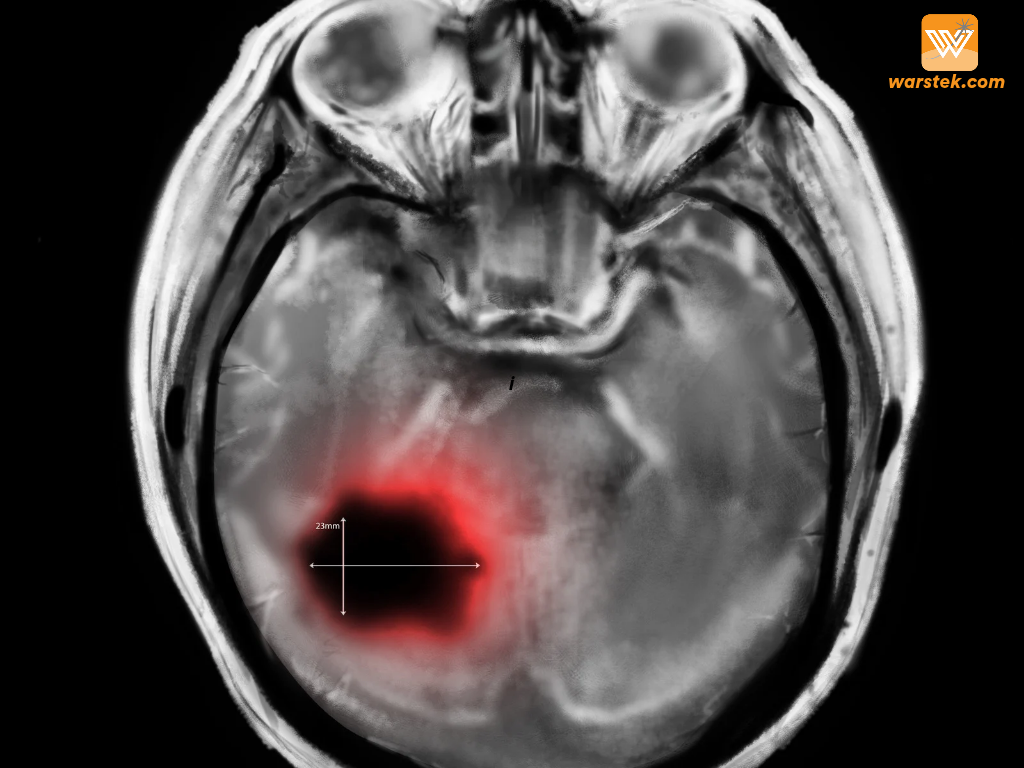

XPO1: Titik Lemah yang Bisa Jadi Kunci Mengalahkan Kanker Otak Anak

Kanker pada anak-anak selalu menjadi momok yang menakutkan, apalagi ketika jenis kanker tersebut langka, agresif, dan sulit diobati. Salah satunya […]